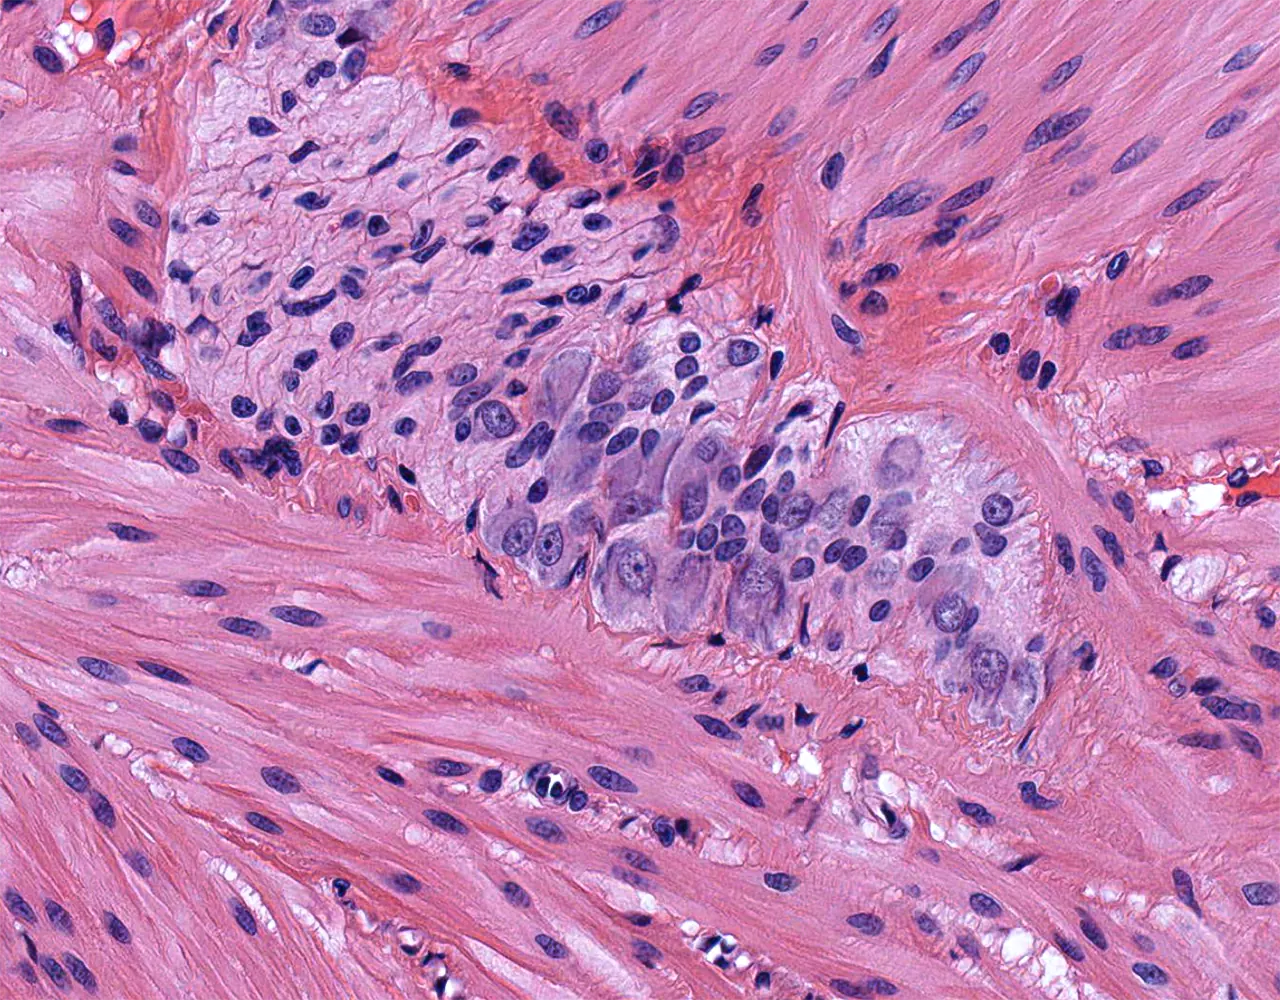

- The absorptive surface area of the small intestine is amplified by three structural levels: plicae circulares, villi, and apical microvilli forming the brush border.

- Microscopically, the wall is composed of 4 layers from the inside outward: mucosa, submucosa, muscularis propria, and serosa.